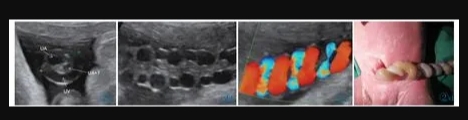

11 例中孕期超聲均可見2 條UA(膀胱水平橫切面顯示2 條UA 血流信號),超聲最后一次提示可見2 條UA 的平均孕周為(31.2±3.1)周。11 例超聲首次提示UA 數(shù)目異常(表現(xiàn)為膀胱水平橫切面UA彩色多普勒僅顯示1 條UA 及血流信號,另一側(cè)血流信號消失)的平均孕周為(36.7±2.8)周,6 例(54.4%)為膀胱左側(cè)血流信號消失,5 例(45.5%)為膀胱右側(cè)血流信號消失。7 例(63.6%)孕晚期超聲首次即提示單條UAT,這7 例臍帶游離段橫切面二維灰階圖像均顯示3 個管腔結(jié)構(gòu),其中1 條UA 內(nèi)可見稍高回聲填充且血流信號消失(圖1);1 例(9.1%)在孕34+4周提示單臍動脈,在孕37 周超聲隨訪中糾正診斷為單條UAT,因超聲提示臍帶高度螺旋,且在臍帶橫切面下見臍靜脈呈“C 形”包繞2條UA,1 條UA 內(nèi)存在血栓回聲(圖2),該病例同時合并胎兒生長受限;3 例(27.3%)整個孕期均提示單臍動脈,回顧其既往中孕期超聲均見2 條UA,晚孕期超聲發(fā)現(xiàn)1 條UA 內(nèi)存在血栓回聲(圖3)。

圖3 誤診為單臍動脈病例的超聲圖像。圖3a:孕24+4 周,膀胱兩側(cè)均可見UA 血流信號;圖3b:孕37+1 周,膀胱一側(cè)UA 血流信號消失;圖3c:臍帶橫切面見臍靜脈呈“C 形”包繞2 條UA,箭頭所示其中1 條UA 管腔細小,內(nèi)為稍高回聲(血栓)填充。圖4 臍帶病理(HE 染色)。UA 內(nèi)見血栓形成,管壁彈力纖維梗死。Figure 3.Ultrasonography misdiagnosed as single umbilical artery.Figure 3a: At 24+4 weeks,the blood flow of two UAs is seen in both sides of bladder.Figure 3b: At 37+1 weeks,only one UA is seen in the level of bladder.Figure 3c: In the cross section of umbilical cord,two UAs are surrounded by umbilical vein.As indicated by the arrows,one UA has smaller lumen which is filled with a slightly higher echo(thrombi).Figure 4.The pathological finding of umbilical cord (HE stain).The UA lumen is filled with thrombi.The necrosis of elastic fibers are found in arterial wall.

2.4 產(chǎn)時情況及產(chǎn)后病理資料

產(chǎn)時肉眼可見11 例臍帶長度均正常,其中4 例(36.4%)臍帶高度螺旋,1 例(9.1%)帆狀胎盤。7 例產(chǎn)時病歷描述可見1 條UA 外觀全程/部分呈暗紅色,1 例UA 部分呈土黃色,橫斷面均可見血栓形成。3 例病歷資料中未描述臍帶外觀。病理結(jié)果提示11 例臍帶橫斷面均提示有2 條UA,鏡下所見其中1 條UA 內(nèi)血栓形成(圖4)。